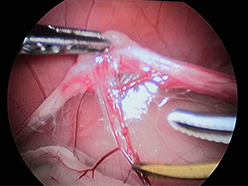

超音波メスにて卵巣動静脈を凝固・切開中です。

精巣側の切開ラインです。腹腔側の切開ラインです。出血は完全に止まっています。

切開後の出血はまったくありません。